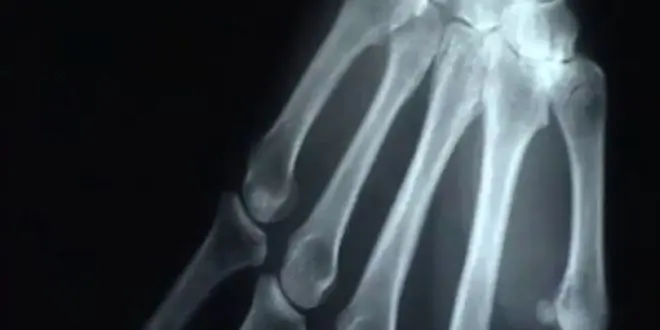

- Les douleurs articulaires au niveau des doigts et poignets, est-ce de l'arthrose forcément ?

Non, cela peut être une polyarthrite rhumatoïde ou d'autres rhumatismes inflammatoires.

- Ma mère de 50 ans souffre d’arthrose aux mains et se soigne aux antibiotiques. Je crois me souvenir que sa mère souffrait du même genre d’arthrose. Est-ce que cela signifie que j’en souffrirais moi aussi ?

Les antibiotiques n'ont jamais été efficaces sur l'arthrose... Le terrain génétique est en effet important dans l'arthrose. Il y a un risque que vous en souffriez mais ce n'est pas forcé !

- Les douleurs articulaires au niveau des doigts et poignets, est-ce de l’arthrose forcément ?

Cela dépend de votre âge (c'est fréquent effectivement chez la femme ménopausée), de vos antécédents (traumatismes articulaires, etc…). A votre médecin de poser le diagnostic.